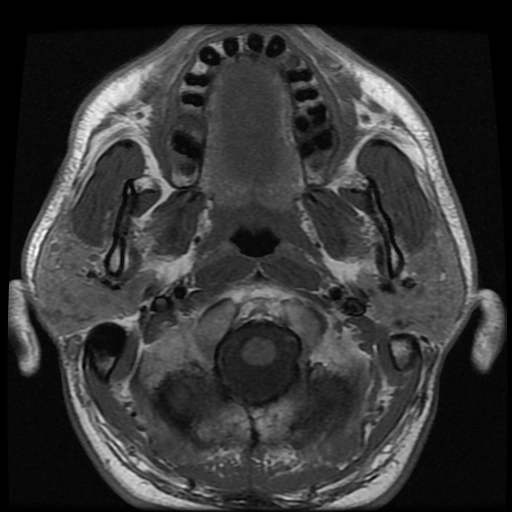

Sỏi tuyến nước bọt (Sialolithiasis)